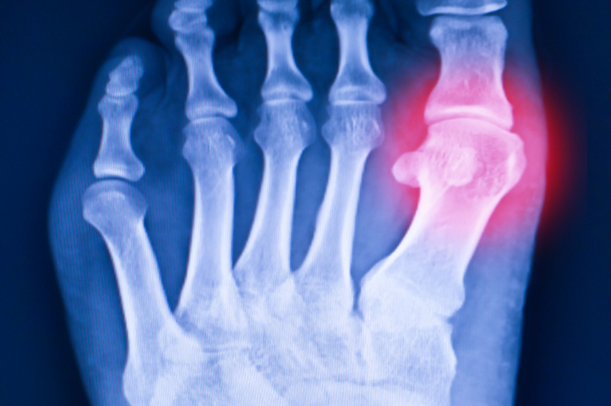

- X線検査(レントゲン):骨の変形や骨折の有無を確認

- MRI:軟部組織(靭帯や腱、軟骨)の損傷をチェック

- 超音波検査(エコー):炎症や腫れの状態をリアルタイムで確認

- 血液検査:痛風やリウマチ、感染性炎症の有無を判断

- 関節穿刺:関節内に炎症や感染がある場合、原因を特定する目的で行うことも

これらの検査を組み合わせることで、痛風以外の病気をより正確に見極めることができると言われています。自己判断に頼らず、早めに専門家へ相談することが安心につながります。